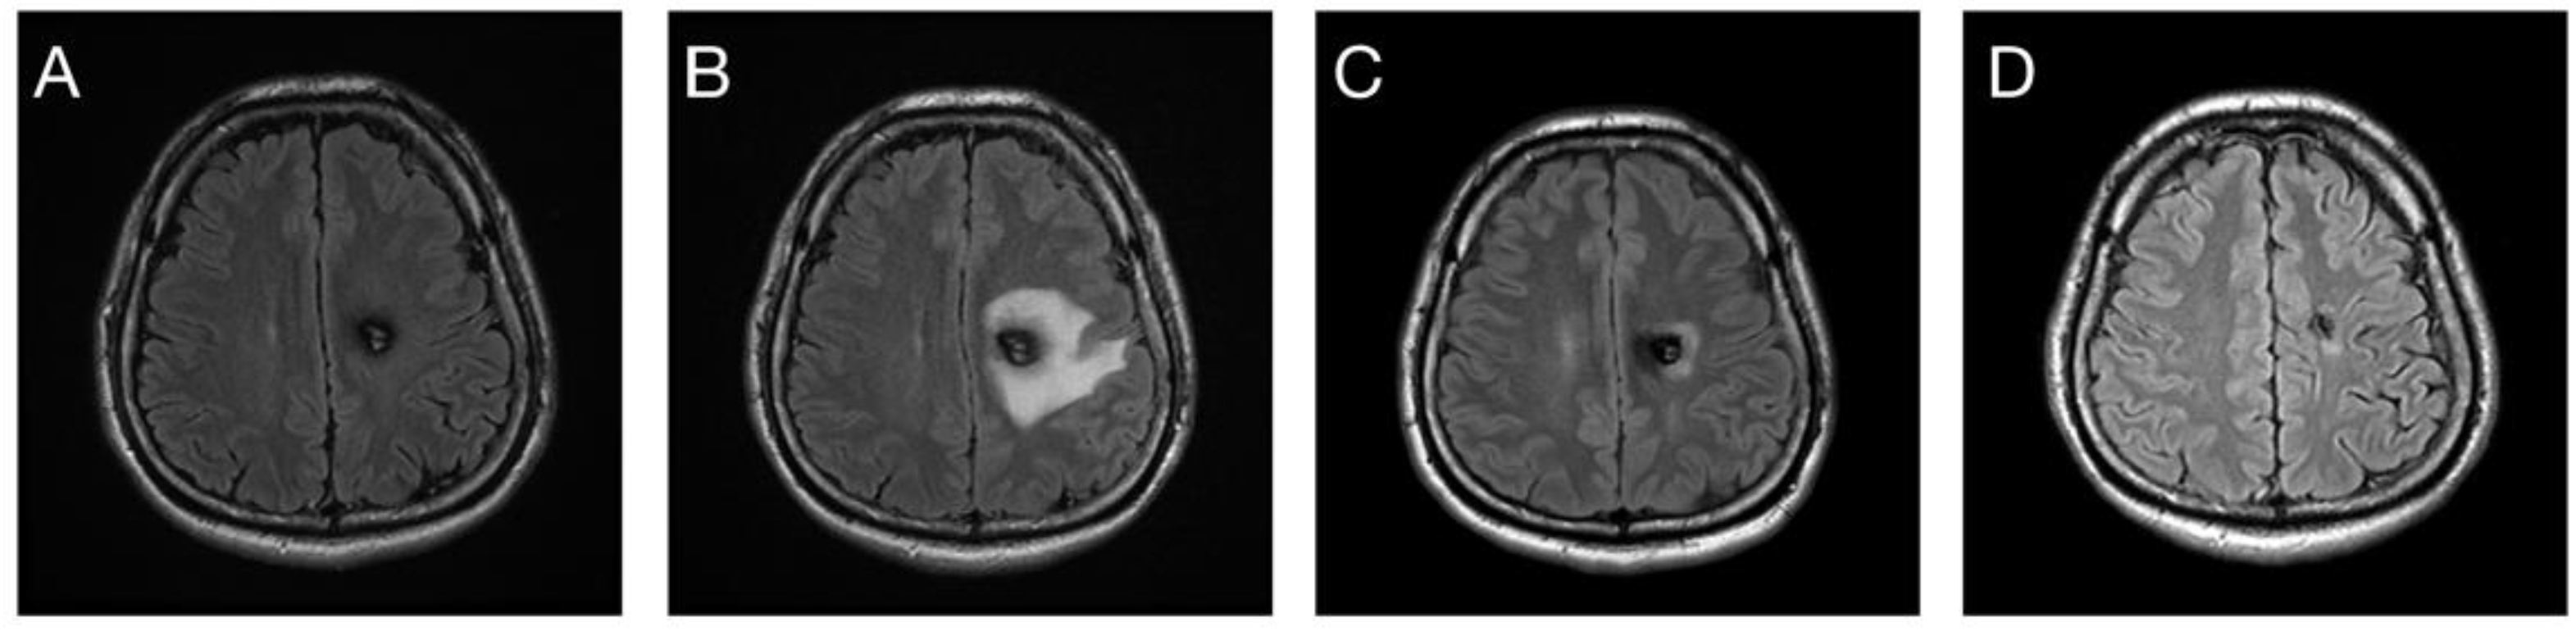

3.3. Response in Volume Control

3.4. Post-Radiosurgical Perifocal Brain Edema

4.2. Post-Radiosurgical Response in Volume Change

4.3. Post-Radiosurgical Adverse Radiation Effects